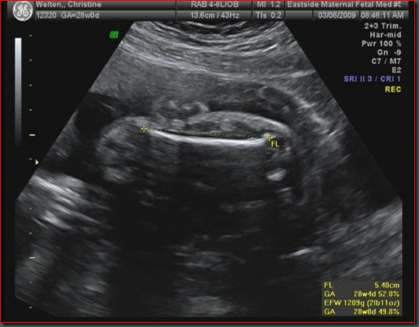

Fetal femur length (FL) is one of the basic biometric parameters used to assess fetal size . Femur length together with biparietal diameter, head circumference, and abdominal circumference are computed to produce an estimate of fetal weight . In the second trimester, this may be extrapolated to an estimate of gestational age and an estimated due date (EDD) .

Femur length (FL) This measures the longest bone in the body and reflects the longitudinal growth of the fetus . Its usefulness is similar to the BPD . It increases from about 1 .5 cm at 14 weeks to about 7 .8 cm at term . (Chart and further comments) Similar to the BPD, dating using the FL should be done as early as is feasible . Femur length calculator

Ultrasound 2009;17(3):161-167 DOI: 10 .1179/174313409X448543 . . . . Femur length dating table (after Altman & Chitty) . 2 . Femur length (mm) GA (weeks z days) 50th centile 5th centile 95th centile . . .

Femur length was slightly less accurate than crown-rump length or BPD . Regression models using a combination of any two or three ultrasonic variables did not improve accuracy of prediction . When ultrasound was used instead of certain LMP, the number of postterm pregnancies decreased from 10 .3% to 2 .7% ( P < .001) .